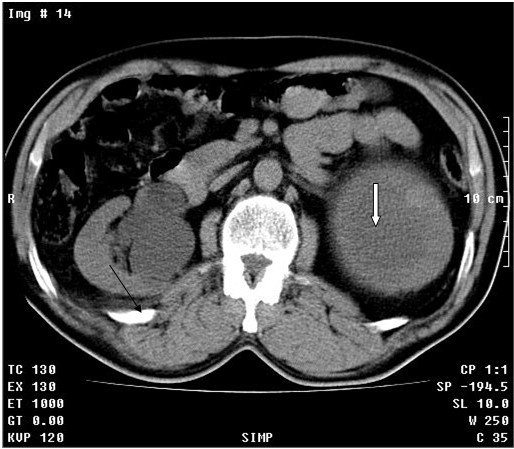

Se realizó tomografía axial computadorizada simple y TAC simple y tomografía con contraste endovenoso y con vistas tardías. Se observó el riñón derecho con dilatación moderada del sistema excretor con posibilidad de quiste asociado (Flecha fina). En el riñón izquierdo se observó proceso expansivo de baja densidad de 13 cm con gruesa cápsula hacia la porción superior del mismo con componente quístico asociado, que provoca retardo en la eliminación del contraste por este lado. (Figuras 1 A, B, C, D flechas gruesas)